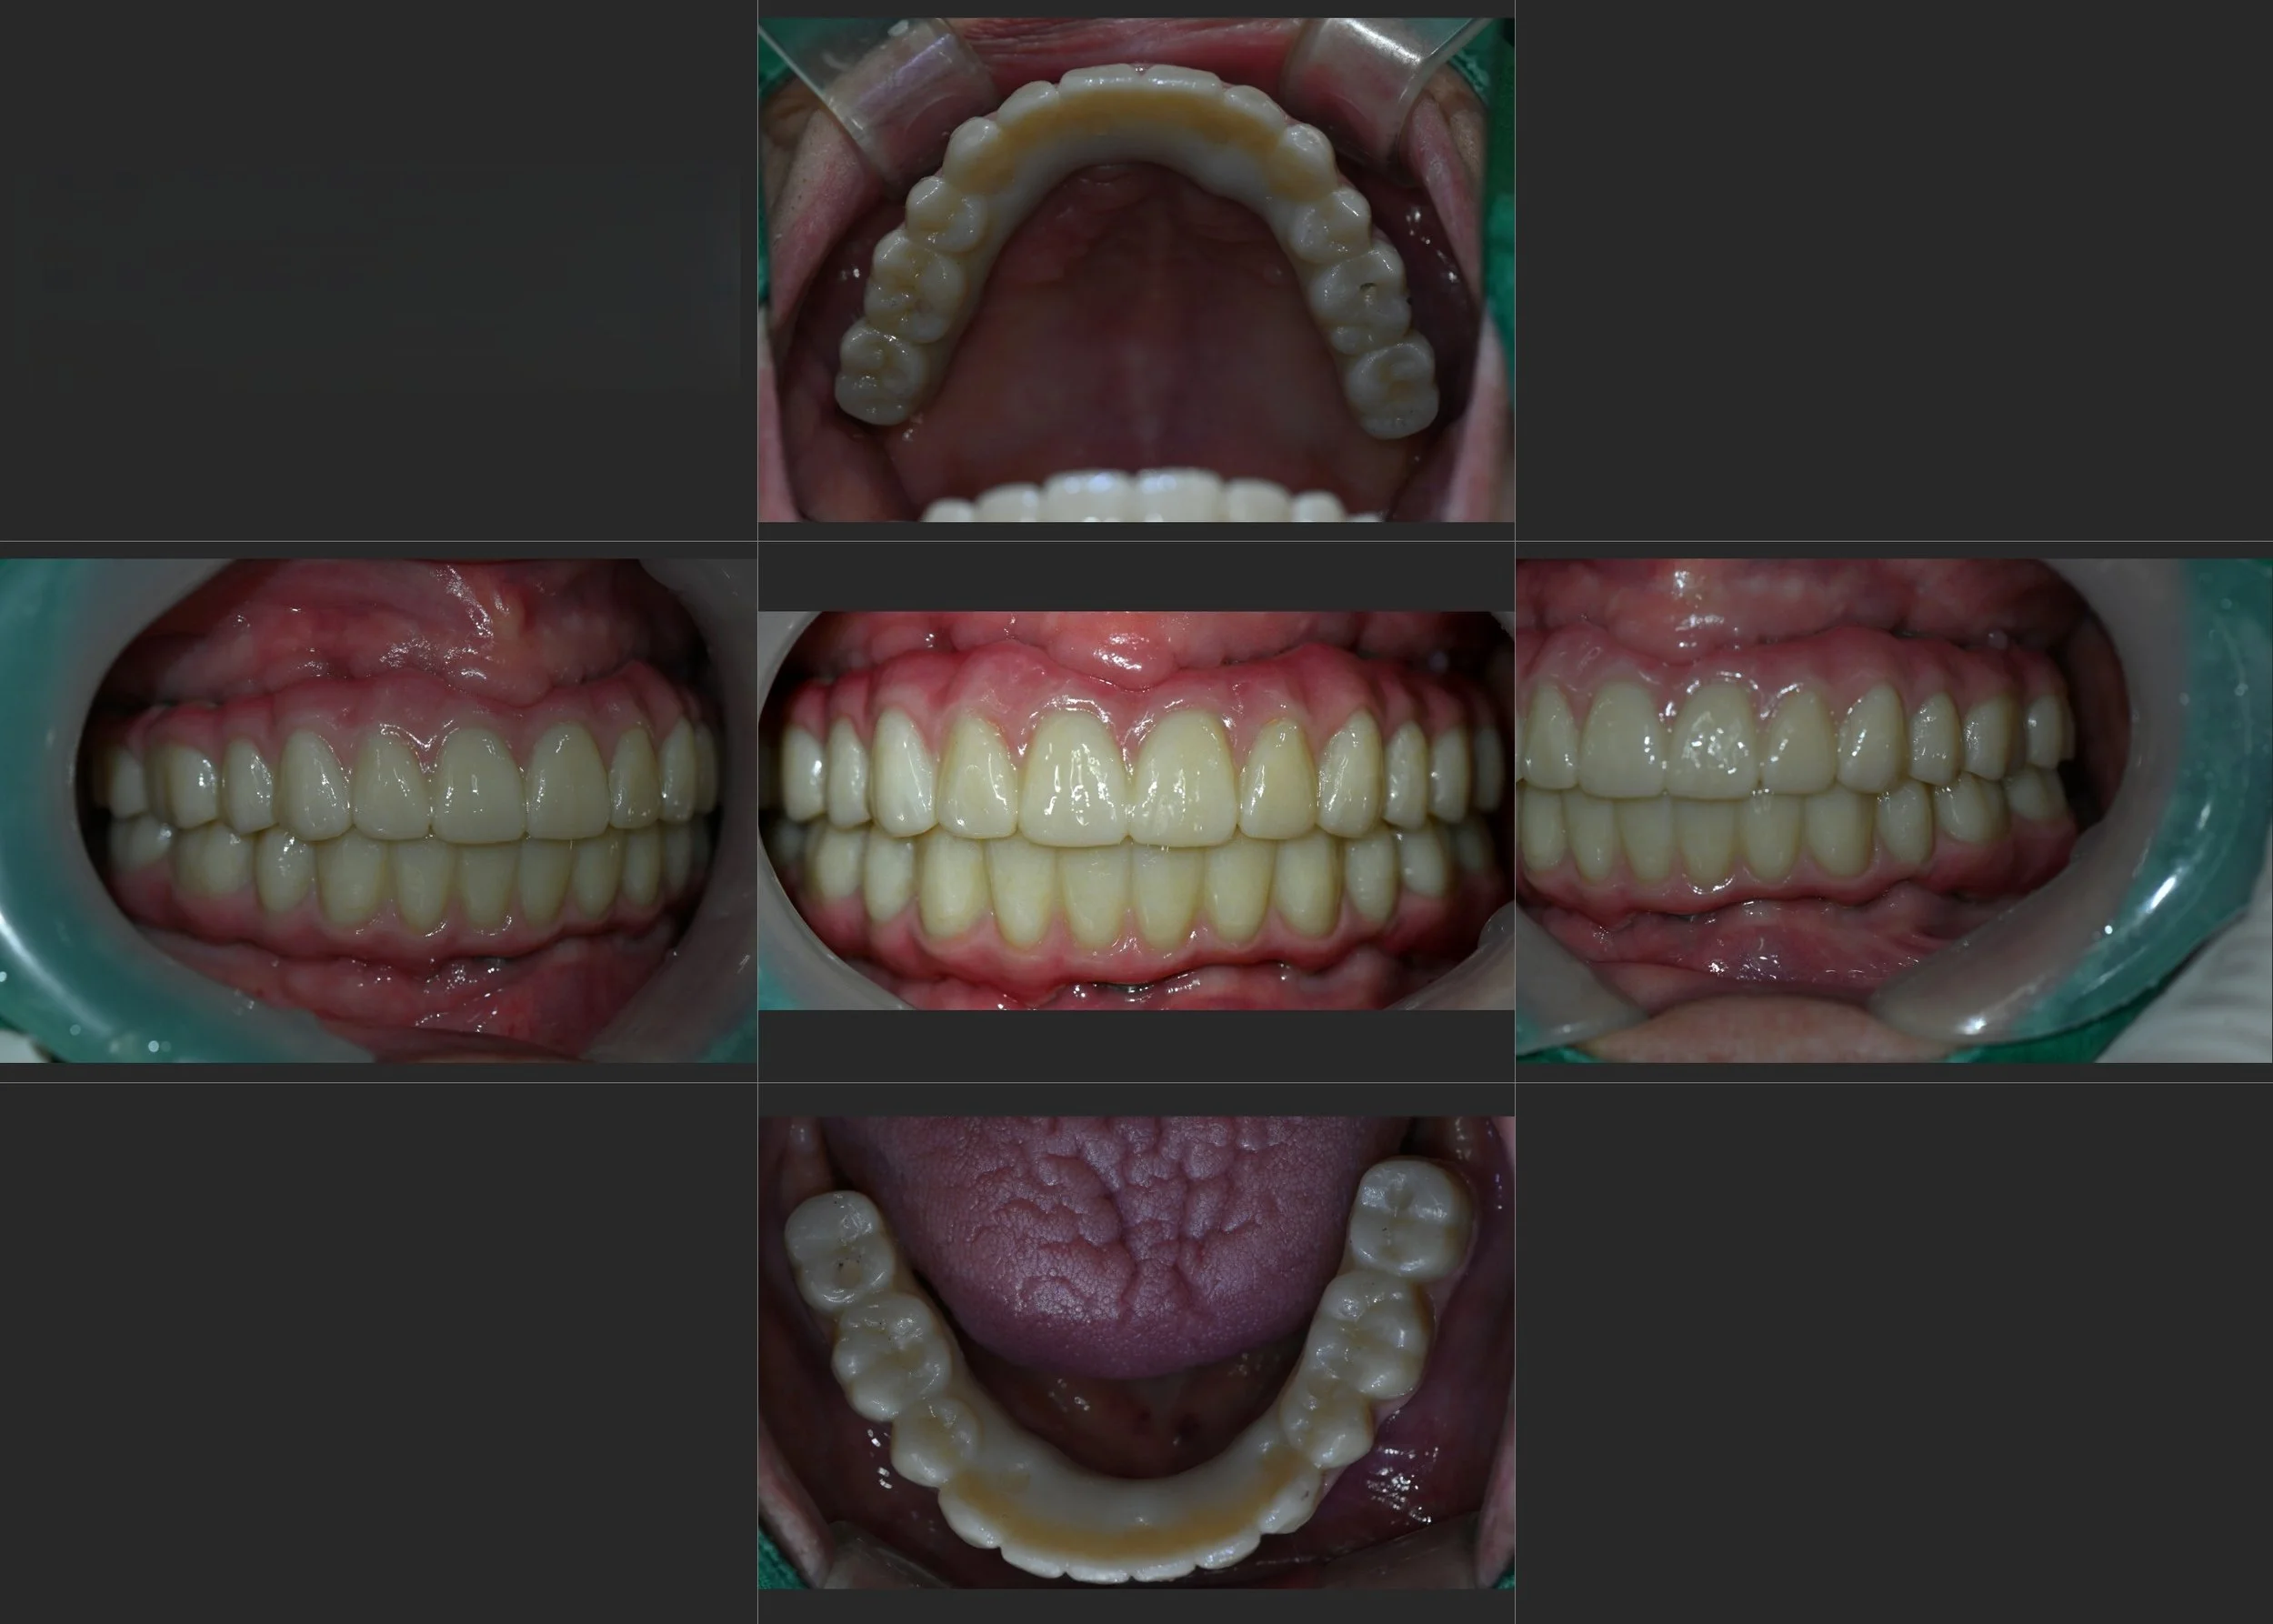

INTRA ORAL - BEFORE

INTRA ORAL - AFTER